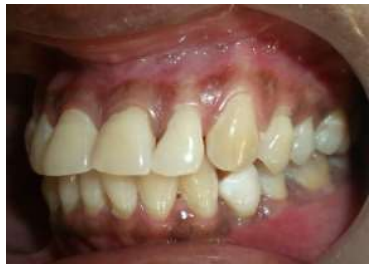

A 34-year-old healthy female patient reported at department of Periodontology and Oral Implantology with a complaint of highly mobile tooth in the lower left region of mouth. Clinical and radiographic findings stipulated it as generalized chronic periodontitis (Fig- 01).

Figure 1: PAN IMAGE

The concerned tooth was lower left first premolar and grade III mobile. 5 It was indicated for extraction. Scaling and root planing was done, and the patient was recalled after 3 days for extraction.   The patient’s tooth got avulsed very next day and she reported back with avulsed tooth. Considering the patient’s request for immediate prosthesis, the idea of natural tooth pontic was proposed. The patient agreed to it and a written signed consent was obtained from her.